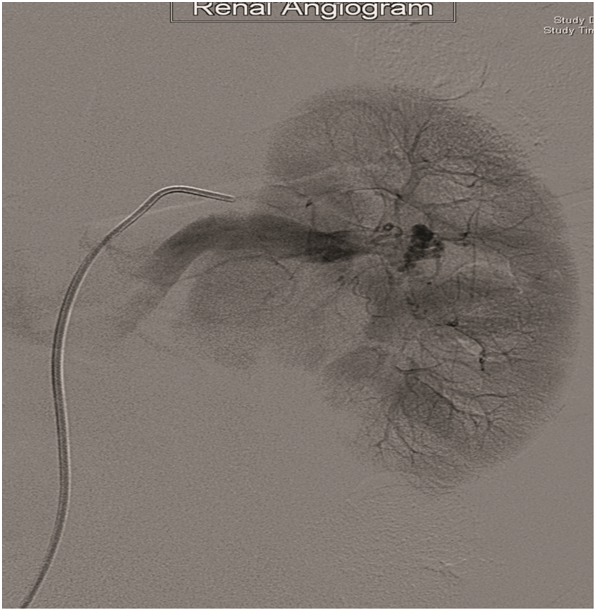

Selective left renal angiography by hand injection revealed a cork-screw like small renal vessels at inter polar region representing nidus of AV malformation with multiple feeding arteries associated with early draining to IVC (Figure 2). Selective embolization of AV malformation was done. Right common femoral artery was accessed with 6Fr sheath and 5Fr guide wire. Different angle angiogram showed multiple feeding arteries. The main Left renal artery feeding branches were occluded by embolizing material Onyx. There were no complications (Figure 3).

Figure 3 Embolization of AV-Malformation.